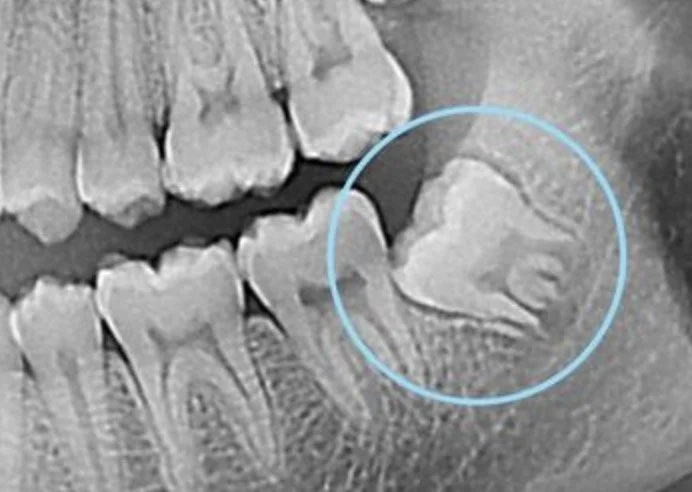

Les dents de sagesse, ou troisièmes molaires, apparaissent généralement entre 17 et 25 ans. Situées tout au fond de la bouche (deux en haut, deux en bas), elles sont parfois absentes, mal positionnées ou n’ont pas assez de place pour sortir correctement.

Dent incluse ou semi-incluse (bloquée sous la gencive ou l’os).

Après analyse radiographique (panoramique ou 3D) permettant d’évaluer la position des dents et les risques éventuels.